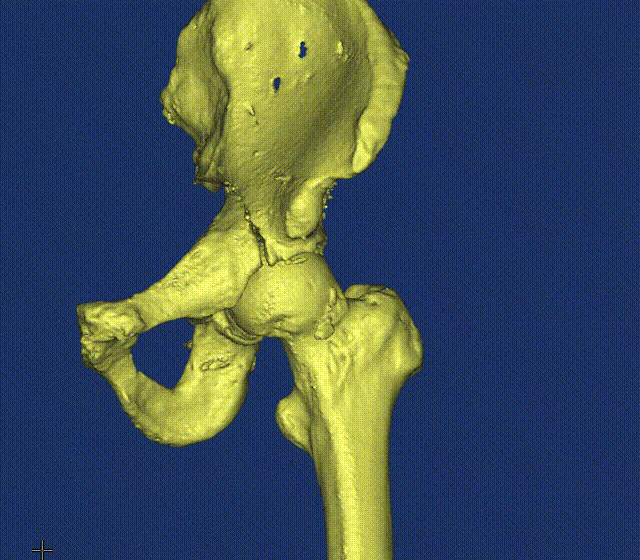

张洪彬医生对患者骨盆三维CT进行了术前虚拟仿真,辅助术者规划骨折复位过程及通道螺钉的置入长度、角度及方向。在患者伤后2周内,由刘利主任主刀,采取单一Kocher-Langenbeck 入路手术入路,术中仔细对坐骨神经及旋股内侧动脉进行了保护,降低了远期发生神经损伤及股骨头缺血性坏死发生风险,完成复位后,应用两块重建钢板及一枚通道螺钉就完成了复杂骨折的固定。术后复查DR及CT骨折复位理想,内固定位置满意,没有发生螺钉进入关节腔的情况。患者得到了早期功能康复锻炼的有利条件。患者现已顺利出院。